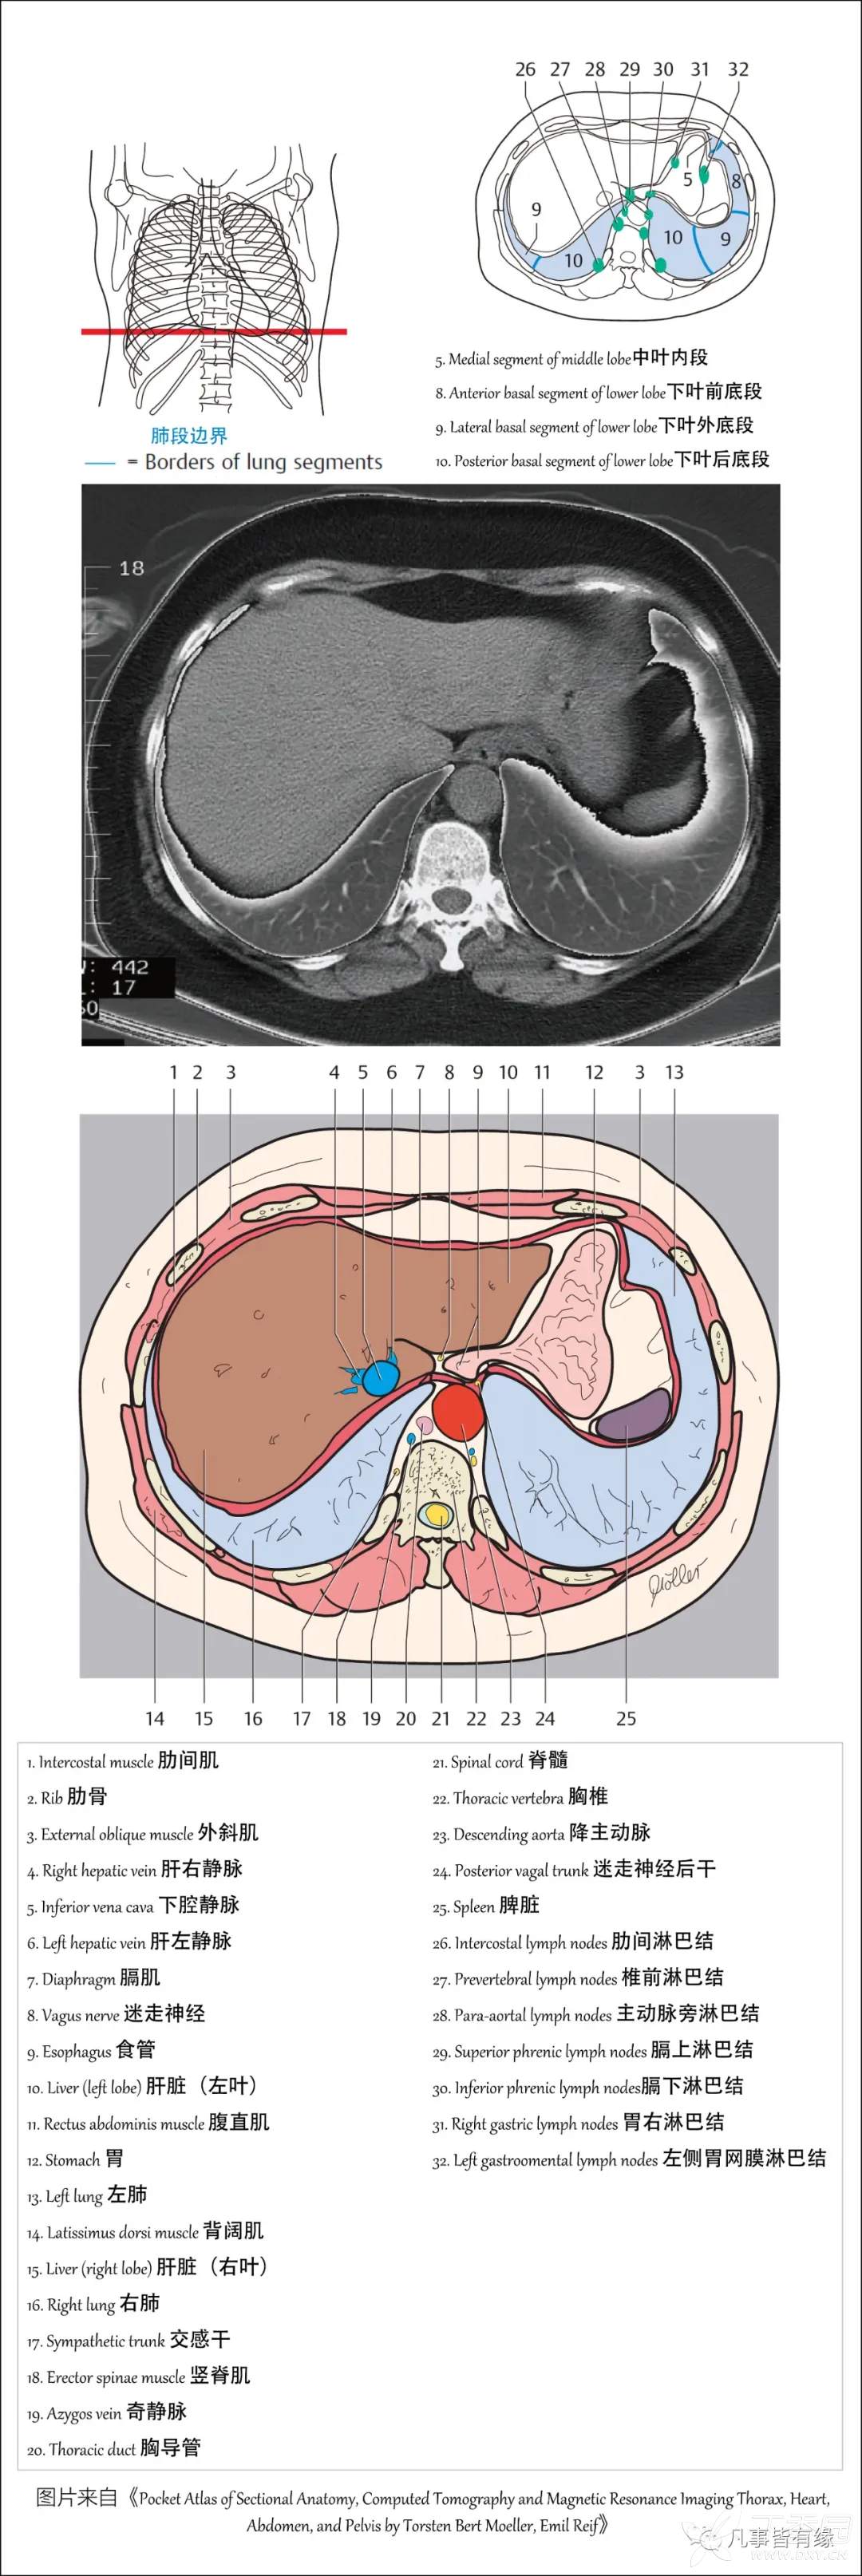

(一)胸部CT轴位断层解剖: